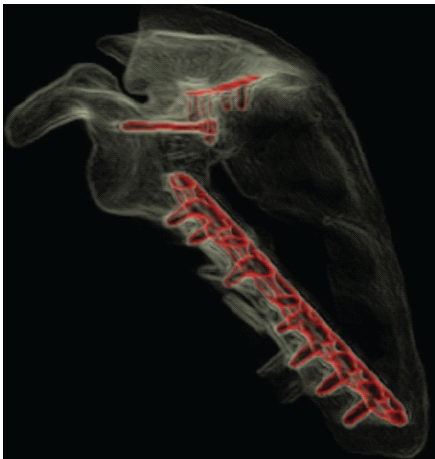

Postoperatively, the patient was immobilized in a sling for 6 weeks. Post-operative radiographs and CT imaging confirmed anatomic reduction and appropriate hardware placement (Fig. 4 and 5). Pain was managed with an epidural and ketamine infusion, and neurorehabilitation planning was initiated. The patient tolerated the procedure well and was discharged with a comprehensive recovery plan.

Figure 5: Post-operative 3D computed tomography reconstruction of the left scapula confirming anatomic reduction and appropriate hardware placement.